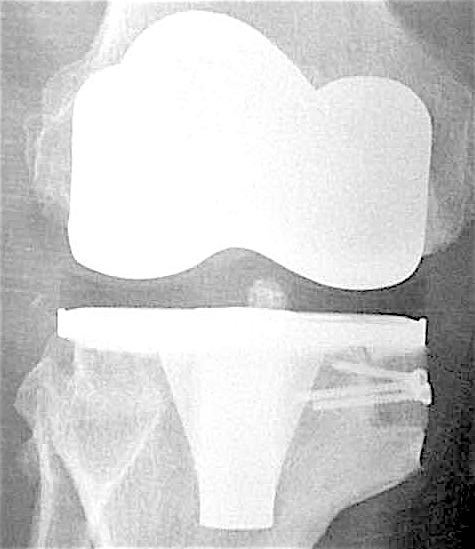

Сделано тотальное эндопротезирование коленного сустава, костная аллопластика материалом «Лиопласт».